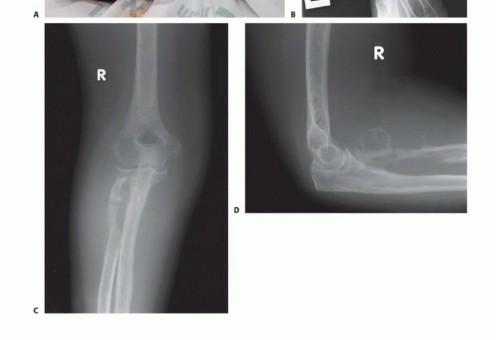

- الأشعة السينية (X-rays): لتقييم العظام وتحديد مدى تلفها أو وجود أورام.

ج. قطع العظم (Bone Transection)

- يتم قطع العظم بدقة عند المستوى المحدد باستخدام منشار جراحي خاص.

- يتم تنعيم حواف العظم لمنع تهيج الأنسجة الرخوة أو الجلد.